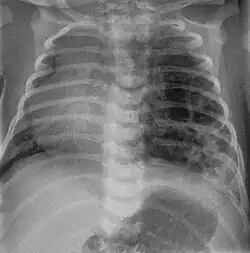

Nach der Geburt: Röntgen der Lunge, CT, ggf. Bronchoskopie, NMR